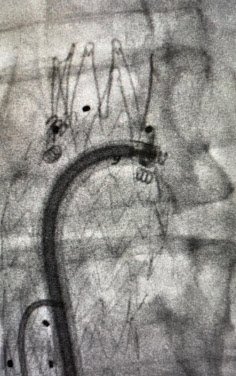

Post-treatment: Endovascular reconstruction with stent placement

Post-treatment

Endovascular reconstruction with stent placement. Restoration of venous flow with symptom resolution.